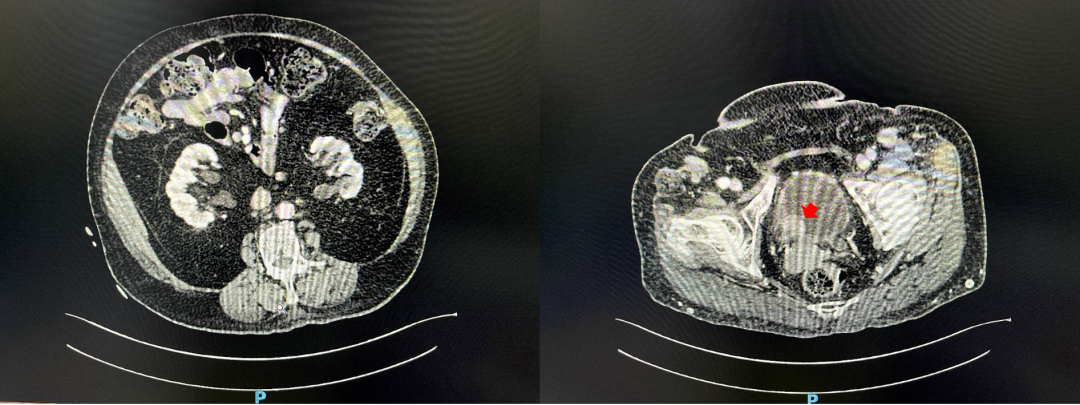

辅助检查:我院CT示“膀胱肿瘤电切术后”膀胱内肿物,考虑膀胱癌,右肾盂及输尿管积水、扩张。CREA:100 umol/L,GFR:55.74 ml/min。

术后半年及1年膀胱镜随访未见异常。术后1年CT随访:“膀胱癌电切术后”膀胱充盈尚可,膀胱壁光滑平整未见明确占位性病变。双侧输尿管无积水扩张,双侧髂脉管区及腹股沟区未见明确肿大淋巴结。